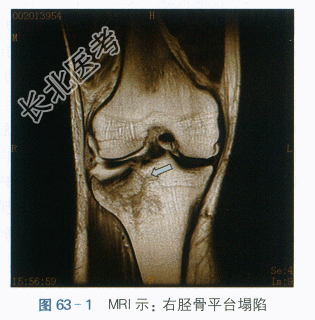

(1)MRI提示:右侧胫骨外侧平台见骨质中断,平台下陷,T1W低信号,T2W稍低信号,STIR为高信号。余所示关节软骨面光整,未见明显缺损。髌上囊及关节腔内见明显量长T1长T2信号积液,滑膜未见明显增厚。右侧膝关节内外侧半月板形态可,T1W中央可见线状等信号灶,未延至关节面,STIR和T2W未见显示。右膝外侧副韧带增粗伴信号增高,髌韧带、股四头肌腱、前后交叉韧带、内侧副韧带形态信号无异常。膝关节周围软组织肿胀。如图63-1所示。